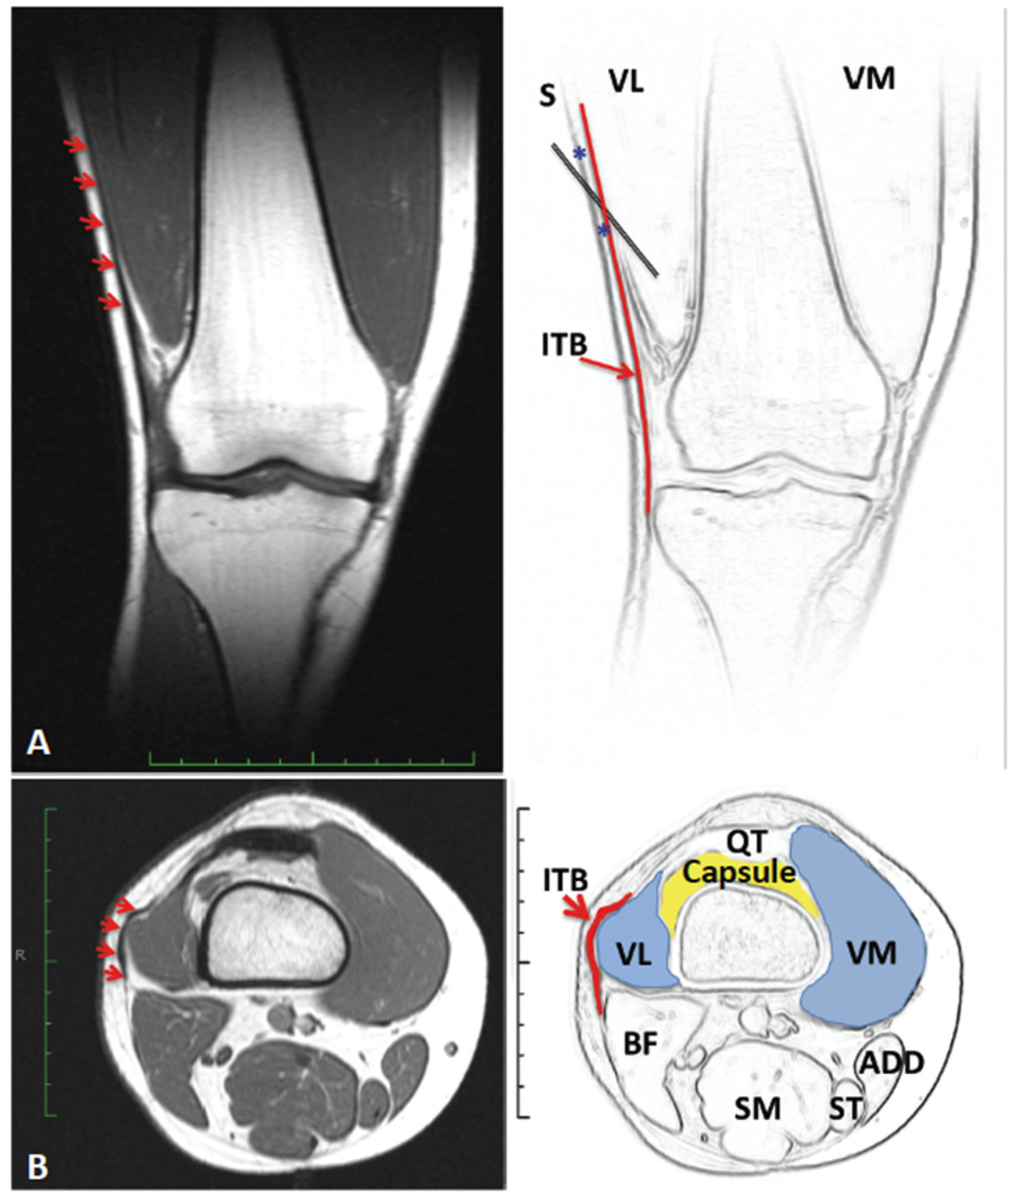

- Singer, B.J.; Silbert, P.L.; Dunne, J.W.; Song, S.; Singer, K.P. Treatment of refractory anterior knee pain using botulinum toxin type A (Dysport) injection to the distal vastus lateralis muscle: A randomised placebo controlled crossover trial. Br. J. Sports Med. 2011, 45, 640–645. [Google Scholar] [CrossRef] [PubMed]